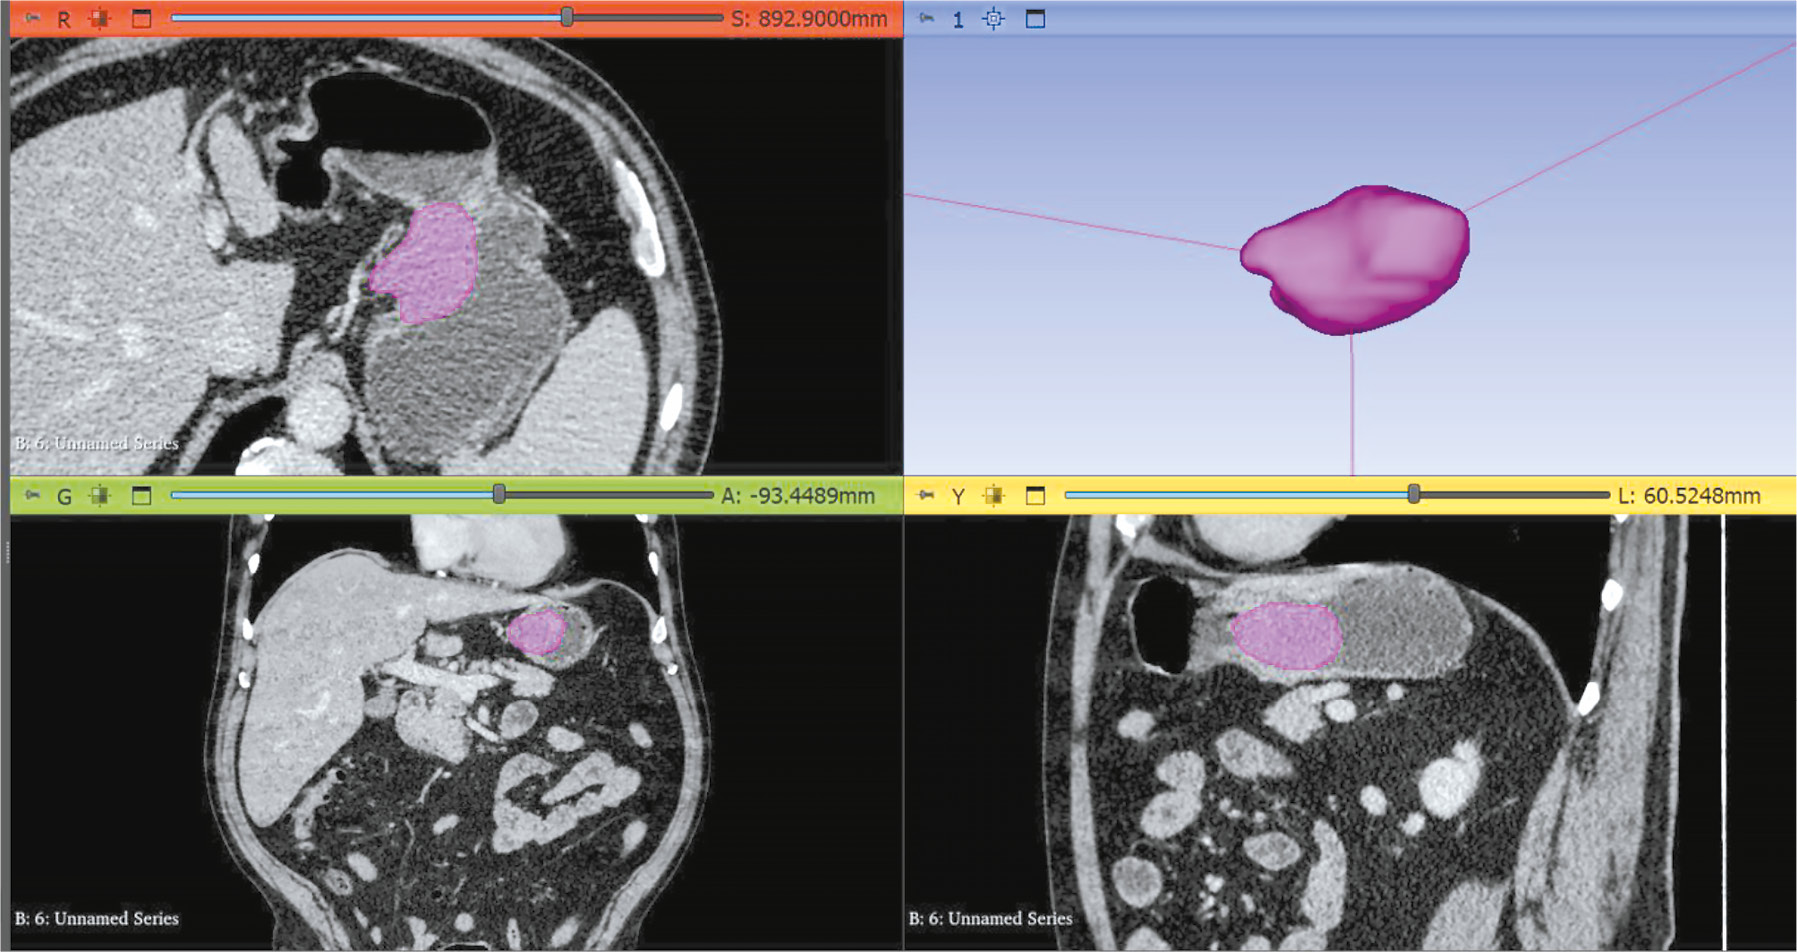

CT angiography dataset with abdominal aorta segmentation

BACKGROUND: Artificial intelligence algorithms are used to analyze images obtained through radiological diagnostic methods. The effectiveness of such algorithms depends on the availability of relevant and representative training datasets. The volume of such data in the public domain should be increased, particularly datasets containing abdominal aorta computed tomography angiography images, with pathology classification and vessel segmentation. The limitations of existing solutions include small sample sizes, restricted dataset specialization, and inconsistent dataset preparation methodologies.

Aim: To create an open dataset containing computed tomography angiography images of abdominal aorta segmentation for normal aorta, aneurysm, thrombosis, and calcification.

MATERIALS AND METHODS: A technical specification for dataset preparation was developed according to the methodology for testing artificial intelligence algorithms, the required sample size was calculated, and approval was obtained from an independent ethics committee. Regarding dataset creation, a previously developed original semiautomatic segmentation algorithm using Slicer 3D software was employed. The inclusion criteria were computed tomography angiography or abdominal computed tomography scans with contrast, arterial phase, and slice thickness ≤3 mm. Conversely, the exclusion criteria were presence of foreign bodies in the aorta lumen and aortic dissection. The algorithm was tested on patient data obtained from the Unified Radiological Information System. An expert evaluation was conducted to assess the compliance of obtained results with the established requirements and evaluate the time efficiency of using the developed segmentation algorithm.

RESULTS: The calculated sample size was 100 angiographic studies, including arterial phase scans with a slice thickness of ≤1.2 mm. Population data: number of unique patients, 100; percentage of female patients, 51%; and median age, 62 years (age range: 18–84 years). Pathology (including combined pathology) was detected in 61% of cases: 60 studies showed signs of calcification, 18 revealed aortic dilation, and 18 determined signs of thrombosed lumen. The average time to process one study (100 slices) using the developed segmentation algorithm was 0.8 hours.

CONCLUSIONS: A dataset containing 100 computed tomography angiography results with abdominal aorta segmentation for normal cases, aneurysm, thrombosis, and calcification was created. The dataset is publicly available and can be used for developing and testing artificial intelligence algorithms and for anthropomorphic modeling of the abdominal aorta.